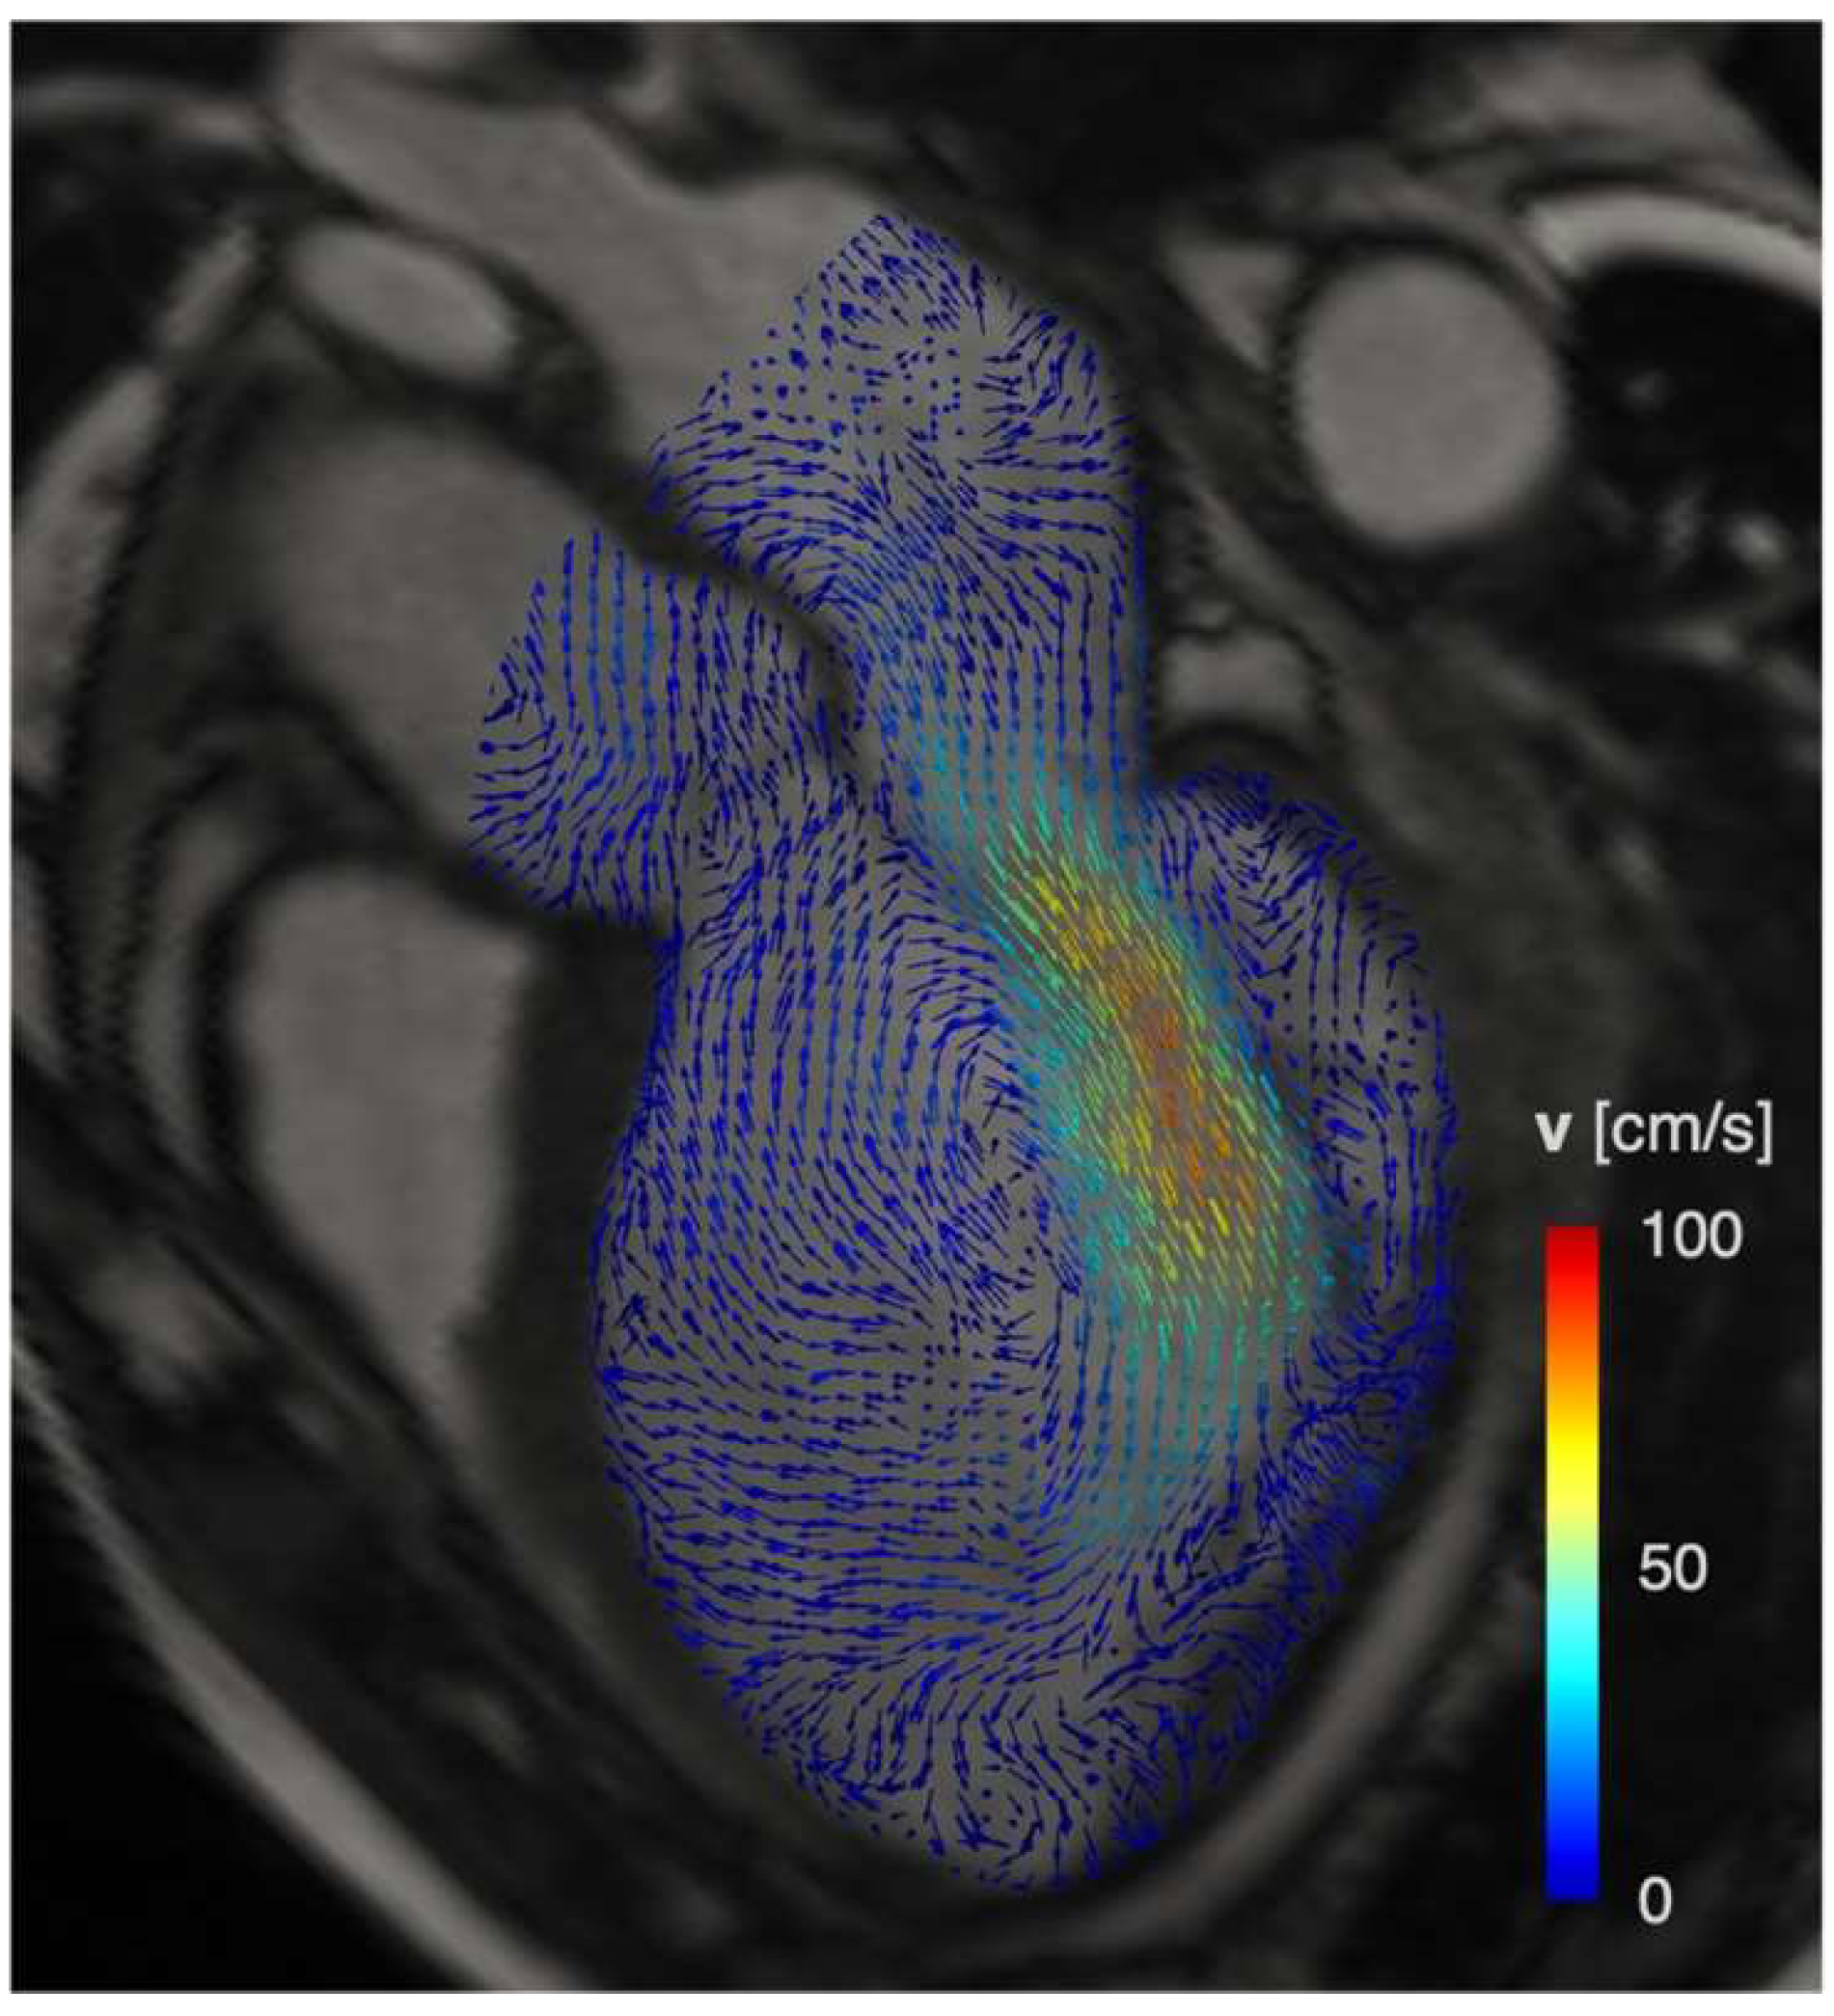

5. 4D Flow Imaging: Intracavitary Blood Flow and Hemodynamic Forces

- Dyverfeldt, P.; Bissell, M.; Barker, A.J.; Bolger, A.F.; Carlhall, C.J.; Ebbers, T.; Francios, C.J.; Frydrychowicz, A.; Geiger, J.; Giese, D.; et al. 4D flow cardiovascular magnetic resonance consensus statement. J. Cardiovasc. Magn. Reson. 2015, 17, 72. [Google Scholar] [CrossRef]

- Garg, P.; Crandon, S.; Swoboda, P.P.; Fent, G.J.; Foley, J.R.J.; Chew, P.G.; Brown, L.A.E.; Vijayan, S.; Hassell, M.; Nijveldt, R.; et al. Left ventricular blood flow kinetic energy after myocardial infarction—Insights from 4D flow cardiovascular magnetic resonance. J. Cardiovasc. Magn. Reson. 2018, 20, 61. [Google Scholar] [CrossRef]

- Filomena, D.; Cimino, S.; Monosilio, S.; Galea, N.; Mancuso, G.; Francone, M.; Tonti, G.; Pedrizzetti, G.; Maestrini, V.; Fedele, F.; et al. Impact of intraventricular haemodynamic forces misalignment on left ventricular remodelling after myocardial infarction. ESC Heart Fail. 2022, 9, 496–505. [Google Scholar] [CrossRef]